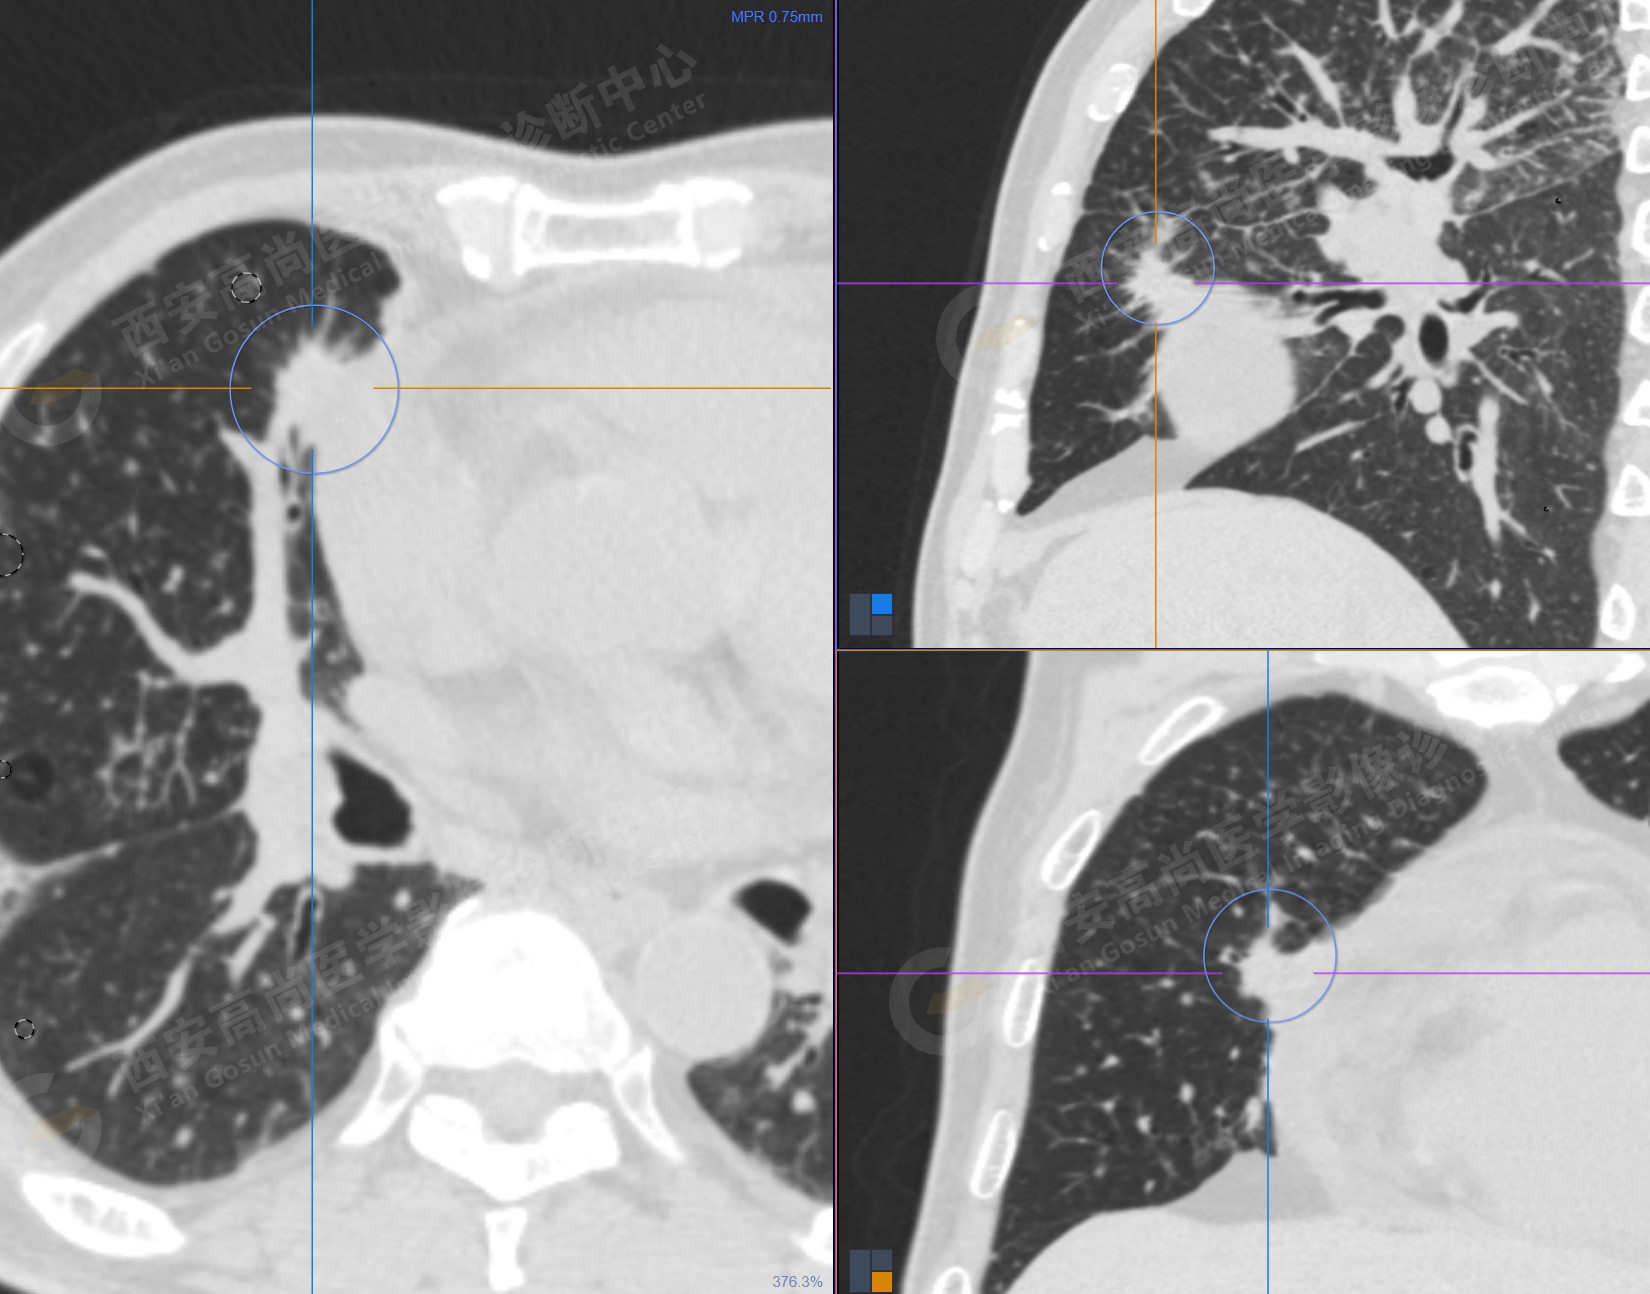

1.以下為肺內原發(fā)灶

1.右肺中葉內側段軟組織結節(jié),呈淺分葉狀,邊緣可見毛刺及胸膜牽拉征,呈FDG代謝異常增高,考慮為周圍型肺癌。